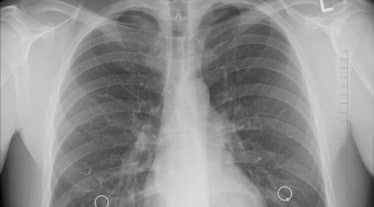

Roche on Friday announced that the European Commission has approved Tecentriq (atezolizumab) as an adjuvant treatment, following complete resection and platinum-based chemotherapy, for adults with non-small cell lung cancer (NSCLC) with a high risk of recurrence whose tumours express PD-L1=50% and who do not have EGFR mutant or ALK-positive NSCLC.

Lung cancer is one of the leading causes of cancer death globally. Each year 1.8 million people die as a result of the disease; this translates into more than 4,900 deaths worldwide every day. According to experts, treating lung cancer early, before it has spread, may help prevent the disease from returning and provide people with the best opportunity for a cure.